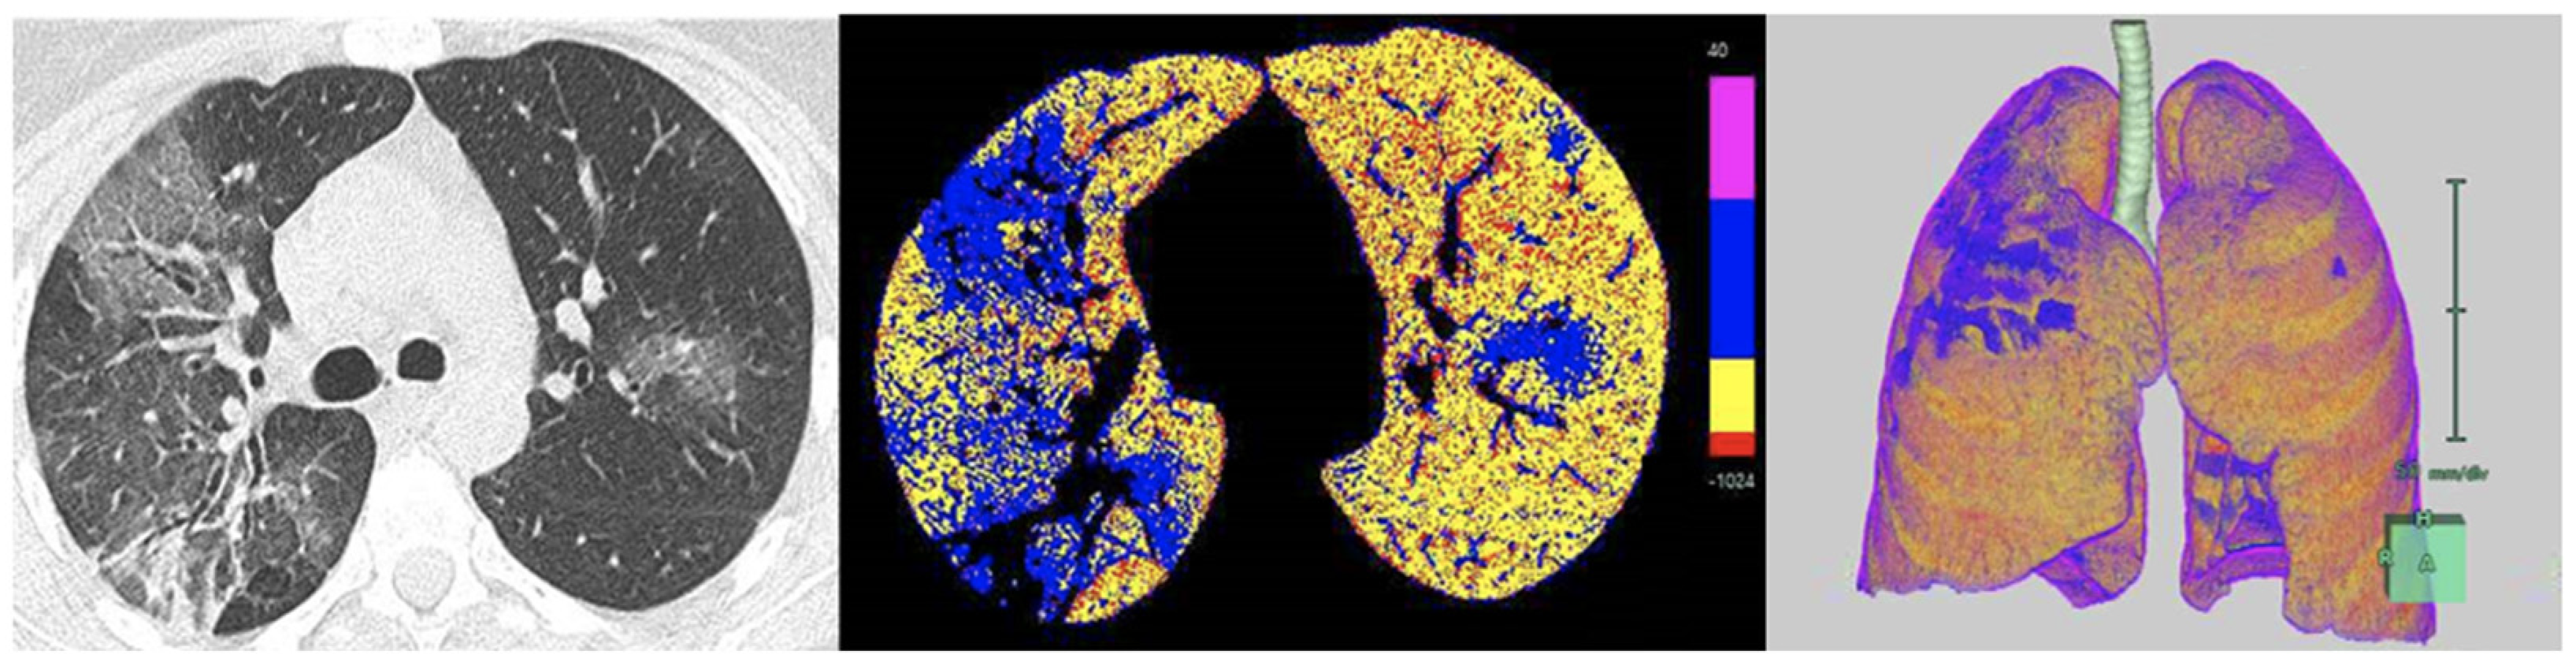

2.4. Density Mask Technique

2.5. Texture Analysis